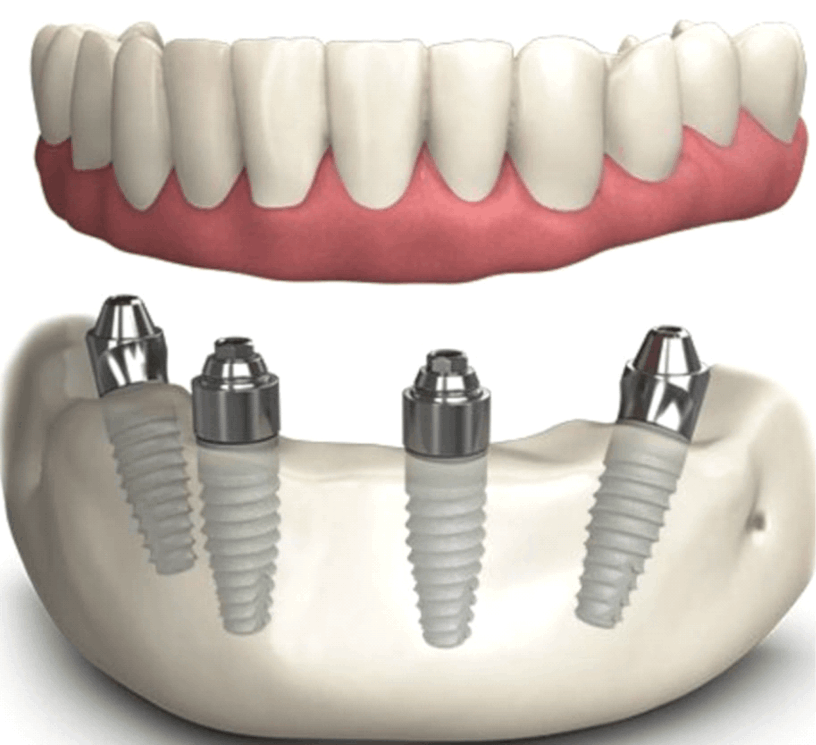

Para se submeter a um implante dentário, o paciente deve ter uma boa saúde bucal, ossos mandibulares saudáveis e estar livre de doenças periodontais ativas. Uma avaliação odontológica é necessária para determinar a viabilidade do implante.

O procedimento é realizado sob anestesia local, o que minimiza qualquer desconforto durante a cirurgia. Algumas pessoas podem sentir um leve desconforto após a cirurgia, mas isso pode ser controlado com analgésicos recomendados pelo dentista.